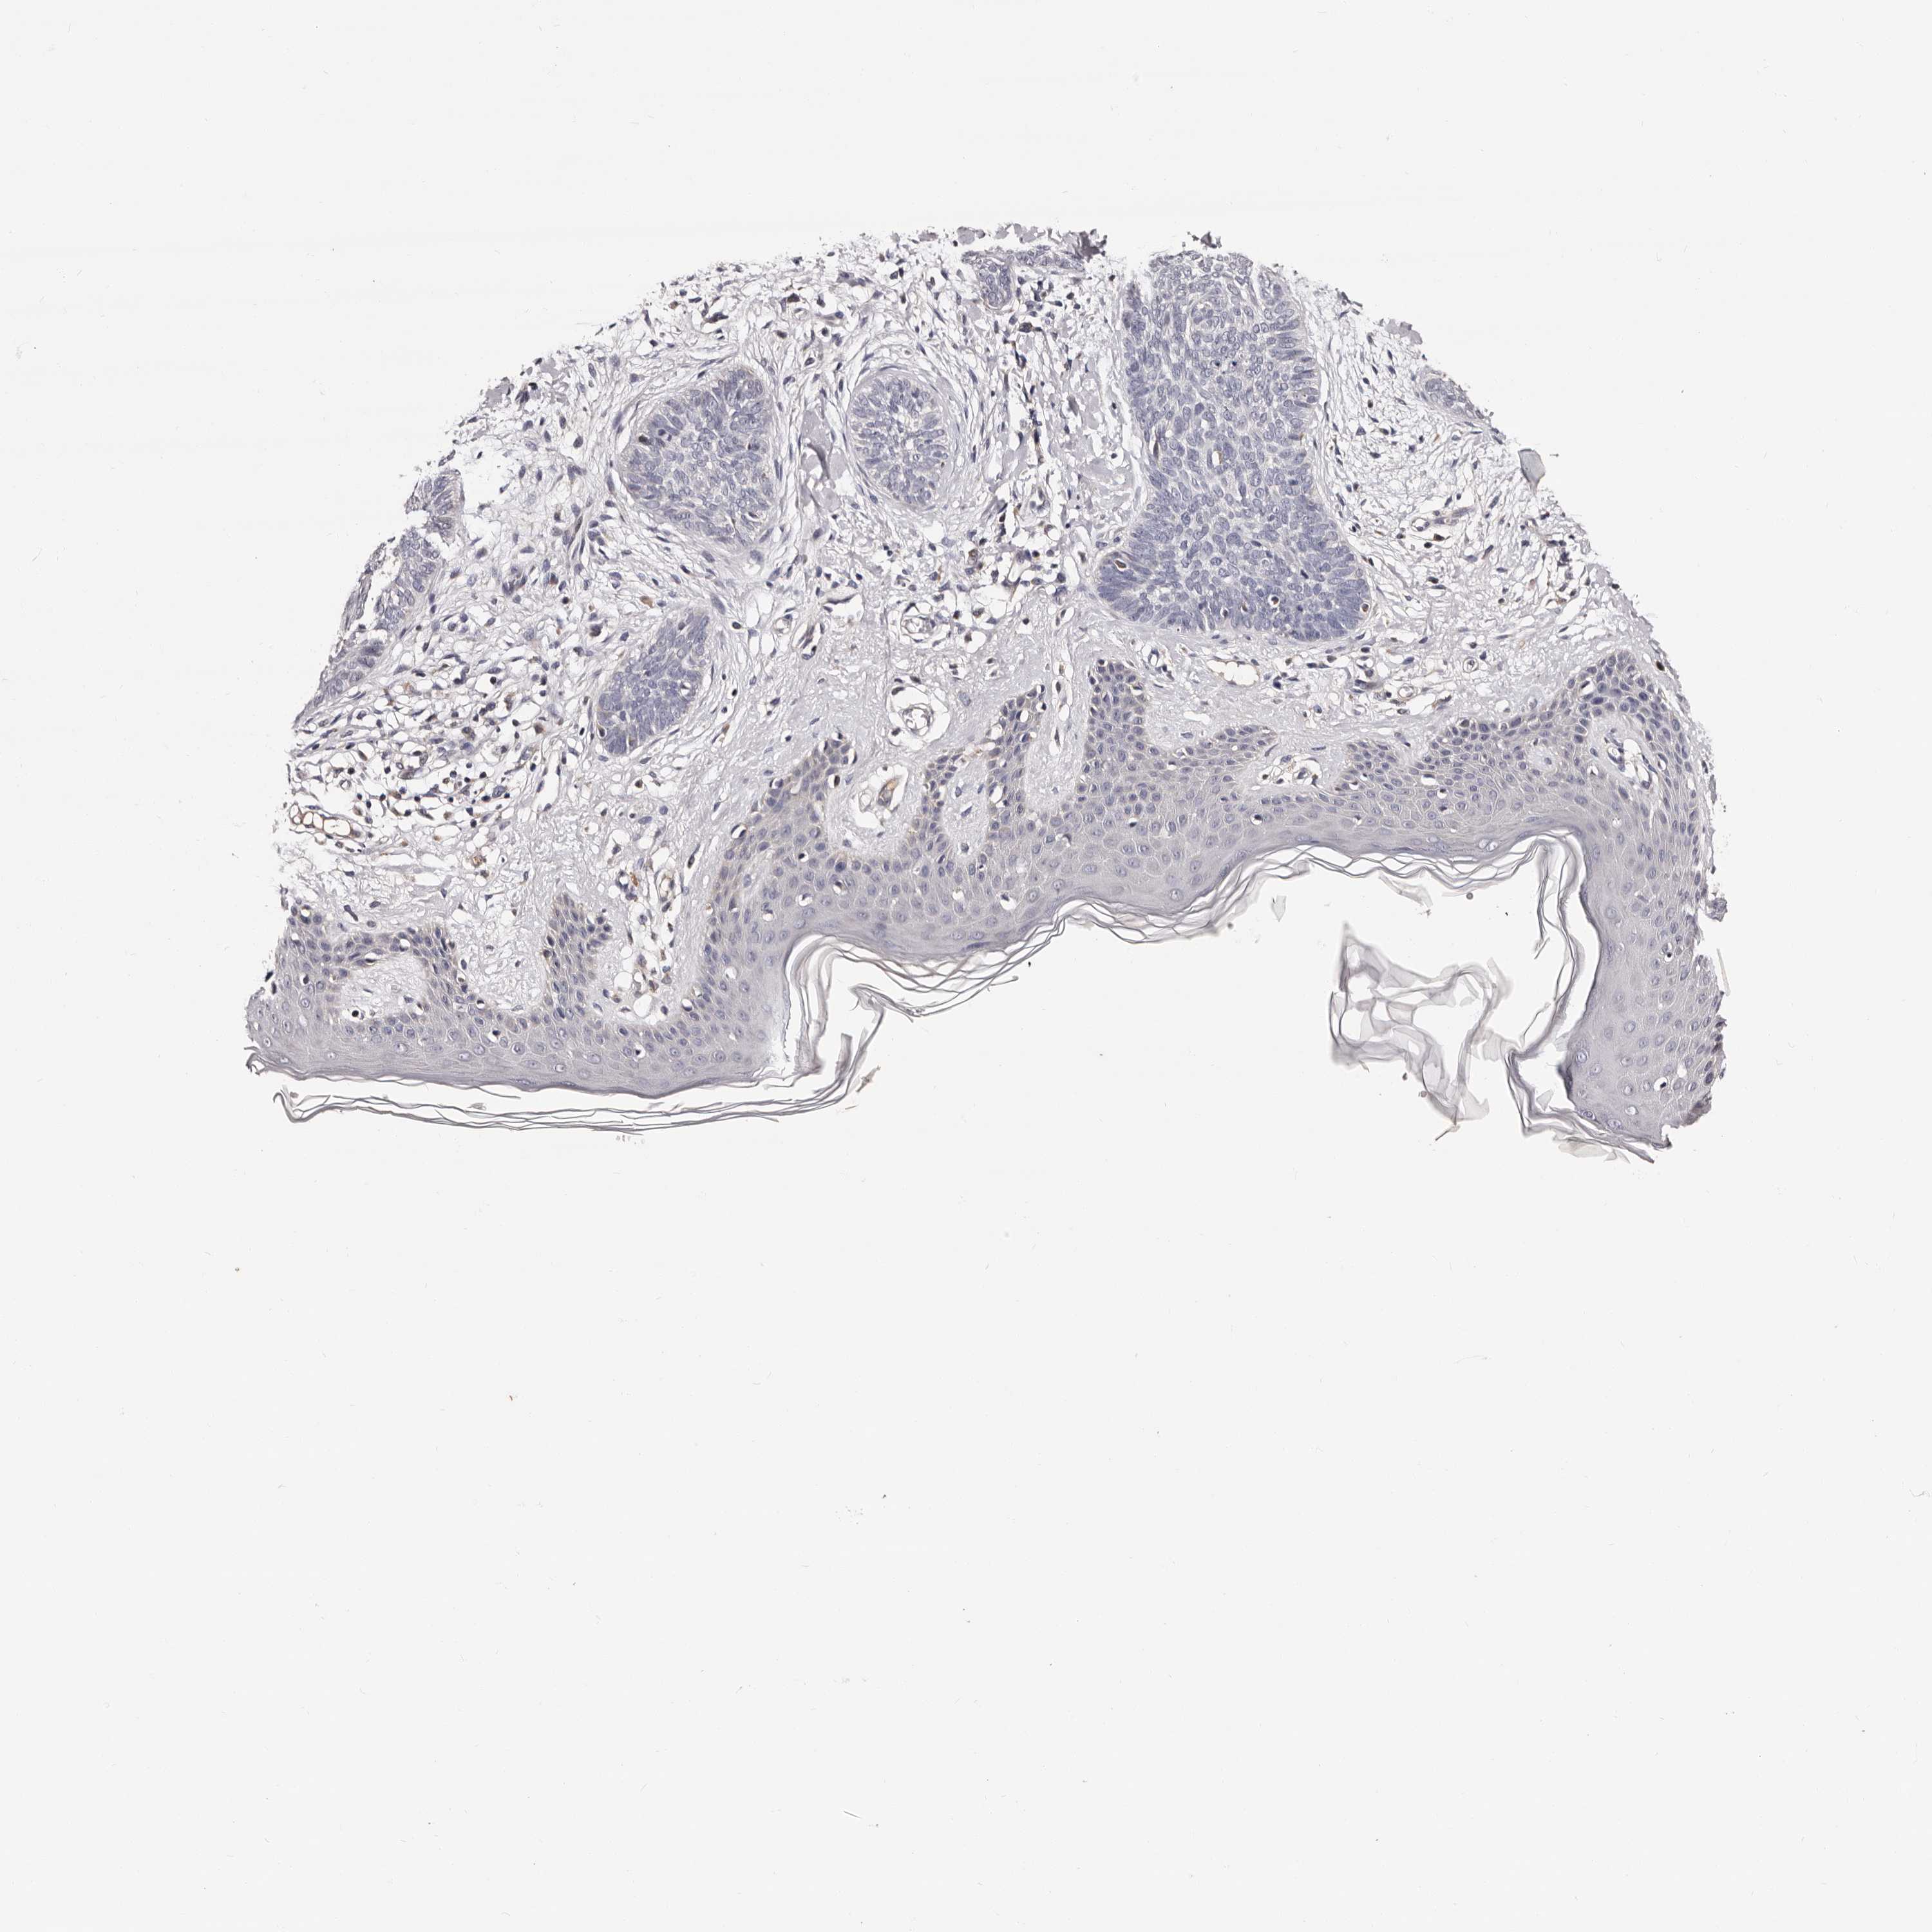

SKIN CANCER - Protein expressioni

A mouse-over function shows sample information and annotation data. Click on an image to view it in a full screen mode. Samples can be filtered based on level of antibody staining by selecting one or several of the following categories: high, medium, low and not detected. The assay and annotation is described here.

Antibody stainingi

Antibody staining in the annotated cell types in the current human tissue is reported as not detected, low, medium, or high, based on conventional immunohistochemistry profiling in selected tissues. This score is based on the combination of the staining intensity and fraction of stained cells.

Each image is clickable and will lead to virtual microscopy that enables deeper exploration of all samples and also displays staining intensity scores, fraction scores and subcellular localization as well as patient and tissue information for each sample.

Antibody HPA028937

Staining

High

Medium

Low

Not detected

Intensity

Strong

Moderate

Weak

Negative

Quantity

>75%

75%-25%

<25%

None

Location

Nuclear

Cytoplasmic/membranous

Cytoplasmic/membranous,nuclear

Squamous cell carcinoma, NOS

Basal cell carcinoma

Adnexal tumor, benign